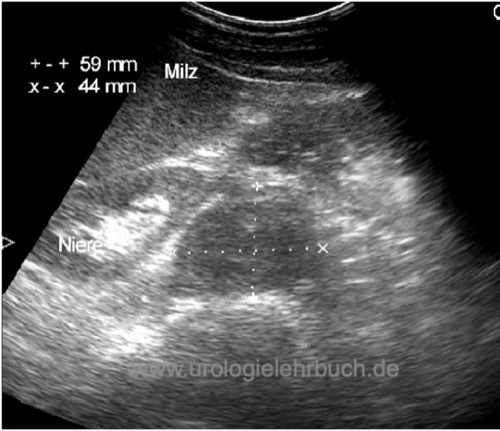

Sonographie Abdomen:

Die Sonographie des Abdomens ist geeignet für eine schnelle Diagnose einer fortgeschrittenen Erkrankung [Abb. Retroperitoneale Metastase im US Abdomen]. Das CT-Abdomen ist sensitiver und kann durch die Sonographie nicht ersetzt werden.